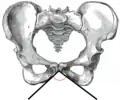

![]() Male pelvis (pubic arch labeled at bottom center) | |

The pubic arch, also referred to as the ischiopubic arch, is part of the pelvis. It is formed by the convergence of the inferior rami of the ischium and pubis on either side, below the pubic symphysis. The angle at which they converge is known as the subpubic angle.[1]

The pubic arch is one of three notches (the one in front) that separate the eminences of the lower circumference of the true pelvis.

The subpubic angle (or pubic angle) is the angle in the human body as the apex of the pubic arch, formed by the convergence of the inferior rami of the ischium and pubis on either side. The subpubic angle is important in forensic anthropology, in determining the sex of someone from skeletal remains. A subpubic angle of 50–82 degrees indicates a male; an angle of 90 degrees indicates a female.[2] Other sources operate with 50–60 degrees for males and 70–90 degrees in females.[1] Women have wider hips, and thus a greater subpubic angle, in order to allow for child birth.

Male subpubic angle